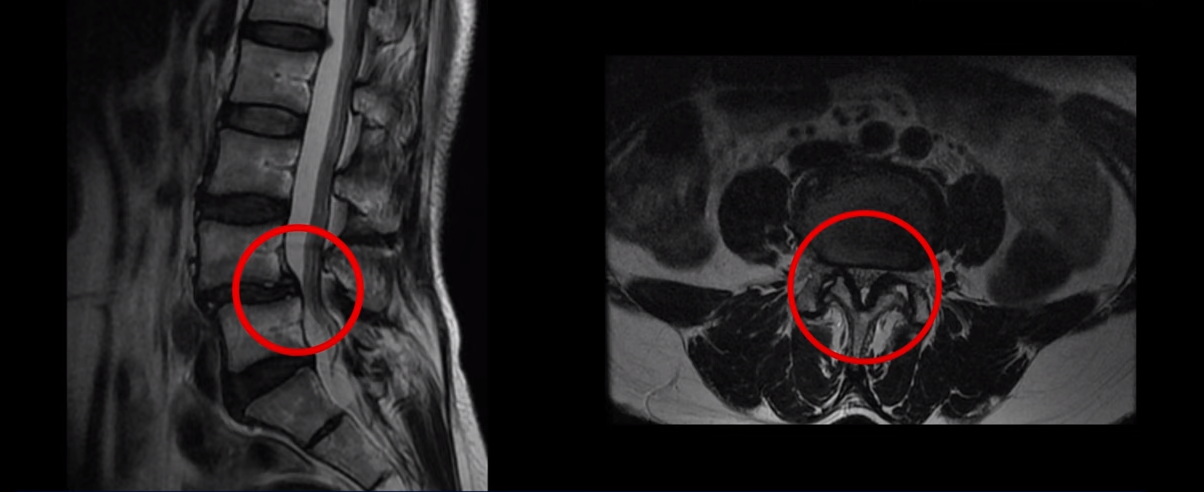

이 환자분은 MRI에서 보시다시피 4번 5번에 전방전위증이 있습니다. 전방전위증이 있는 분들은 디스크 문제나 협착증 문제를 동반하는 경우가 많은데 이분은 4,5번 디스크에 큰 문제는 없으시고 척추관이 약간 좁아져 있으나 다리 쪽의 증상은 전혀 없고, 오로지 만성허리통증만 있습니다. 3년 동안 허리가 심하게 아프신 상태입니다. 참고로 이분은 심하게 넘어지면서 엉덩이 근육 파열로 입원하신 상태에서 만성 허리통증 치료를 함께 받으셨습니다. 그런데 저희가 만성 허리통증이 있는데 ‘허리에 디스크가 보이든, 협착증이 보이든, 전방전위증이 보이든, 만약 다른 증상 없이 허리 통증만 있다면 그건 근육의 문제일 가능성이 매우 높다’고 여러 영상에서 설명 드렸습니다. 이분을 처음 진찰했을 때 허리 주변 근육들과 엉치 근육을 꼼꼼히 만져보았는데 역시 허리통증과 연관되어있는 중요한 근육들, 장요근, 요방형근, 기립근, 둔근이 모두 다 심하게 굳고 뭉쳐있었습니다.